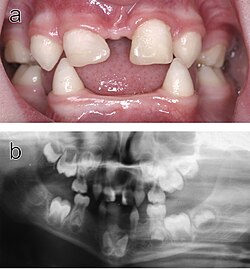

Ektodermal displazi, ektodermadan yaranan toxuma qruplarının (xüsusən dişlər, dəri, saç, dırnaqlar və tər vəzləri) anormal inkişafa məruz qaldığı nadir, lakin ciddi bir vəziyyətdir. Bu, qeyri-müəyyən bir müddətdir, çünki 170-dən çox ektodermal displazi var. Xəstəliyin bir mutasiya və ya müəyyən genlərdəki mutasiyaların birləşməsindən qaynaqlandığı qəbul edilmişdir. Ektodermal displazi alt tipi ilə əlaqəli mutasiyaların yalnız bir hissəsi müəyyən edildiyi üçün bu xəstəliklə bağlı araşdırmalar davam edir . Hipohidrotik ektodermal displazi (HED) xəstəliyin ən çox yayılmış alt tipidir. Klinik hallarda, bu xəstəlik olan xəstələrdə bir sıra simptomlar var. Hipohidrotik ektodermal displazi normasından ən əhəmiyyətli hipohidrozdur, tər vəzlərinin olmaması və ya funksiyasının pozulması səbəbindən kifayət qədər tər istehsal edə bilməməsidir. Bu cəhət, xüsusən də yayda ciddi bir dezavantajdır, xəstənin həm idman etmə qabiliyyətini həm də işləmək qabiliyyətini məhdudlaşdırır və xəstələrin həyati təhlükəsi olan hipertermi riski altında olduğu isti iqlimlərdə xüsusilə təhlükəli ola bilər. Üzün qüsurları Hipohidrotik ektodermal displazi ilə də əlaqələndirilir, məsələn, sivri və ya itkin dişlər, göz ətrafındakı qırışmış dəri, seyrək və incə saçlarla birlikdə səliqəsiz burun forması. Bəzi hallarda ekzema kimi dəri problemləri də müşahidə olunur . Xəstələrin çoxu X xromosomunda EDA geninin variantlarının daşıyıcısıdır. Bu vəziyyət ümumiyyətlə kişiləri daha ciddi şəkildə təsir edir, çünki onlarda yalnız bir X xromosom var, qadınlarda saniyədə təsirlənməyən X xromosomu əksər simptomların qarşısını almaq üçün kifayət ola bilər.